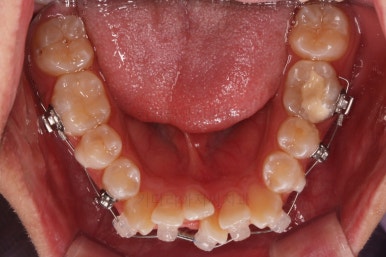

초진 시 입안의 모습입니다.

앞니가 많이 삐뚤고, 송곳니가 부각되어 덧니처럼 보이네요.

장치를 처음 부착한 모습입니다.

순차적으로 장치를 붙여가며 치아를 가지런하게 합니다.

가지런하게 하는 단계를 거친 뒤,당기기 과정에 들어가는데요.

이 과정에서 입이 들어가는 양, 중앙선, 기울기, 앞니 각도 등등 많은 것을 신경써서 당기기를 해주는데요.

다양한 위치/방향/방법으로 치열을 개선해 나갑니다.

환자부니 원하시는 포인트, 디테일을 정리하면서 마무리를 해줍니다.